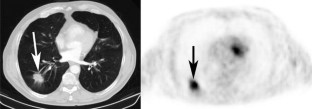

Fig. 2